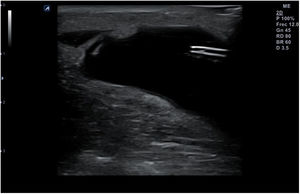

La punción se puede hacer en el eje largo de la sonda, denominada también «en plano» (fig. 14), con la aguja entre 30 y 45° de inclinación respecto a la superficie, lo que permite visualizarla en todo su trayecto, y lo hace muy recomendable cuando haya riesgo de lesionar estructuras cercanas. La aguja aparecerá en la pantalla como una línea hiperecogénica brillante con artefacto de reverberación (al ser un objeto metálico, se dibujarán líneas paralelas hiperecogénicas por debajo de la misma por un efecto espejo). Para poder visualizar correctamente todo el trayecto de la aguja, esta debe orientarse en el mismo plano de corte de la sonda.

En otros casos interesará realizar un abordaje en el eje corto de la sonda, denominado «fuera de plano»(fig. 15) introduciendo la aguja perpendicular a la sonda, en su parte media, de modo que en la pantalla será visible únicamente la punta. Esta técnica no permite seguir el trayecto completo de la aguja en un solo corte, pero ofrece una imagen precisa de su punta. El uso de una u otra técnica dependerá de las preferencias del profesional que realice la técnica, del tipo de punción y de las condiciones anatómicas de la zona.